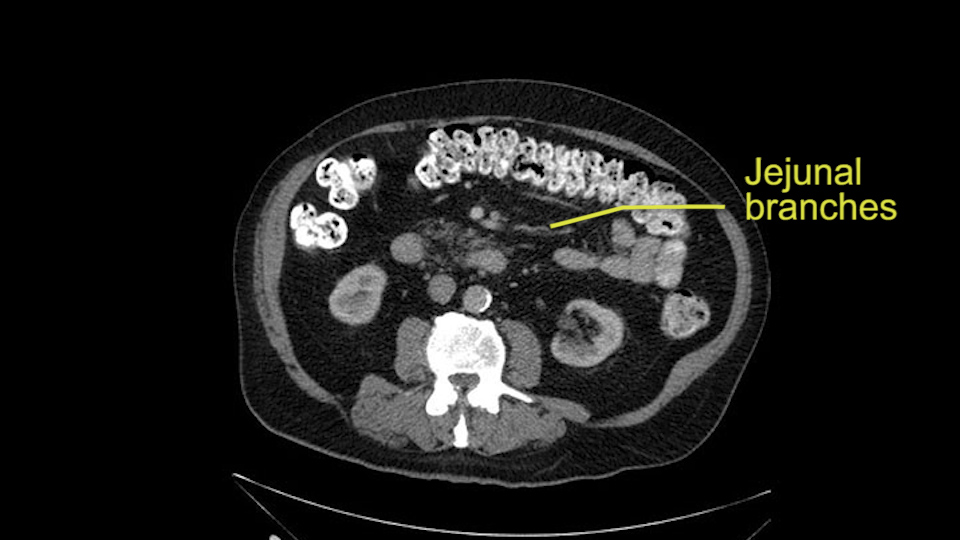

Then look at the first jejunal branch - which is this thing here - this little branch which goes under the SMA. It’s something that we’ve just started appreciating over the past few years and the reason for that is: there’s two or three small branches that come out of the uncinate into the the first jejunal and it’s a fairly inevitable part of the operation where there’s some bleeding. As long as you’re cognizant of what’s happening, it’s no reason to panic and that kind of bleeding will eventually stop or can be stopped but it’s not easy because these little vessels are fragile from the uncinate to the first jejunal. So I do focus on that and it’s pretty consistent I’d say 9 times out of 10, people have that first jejunal.